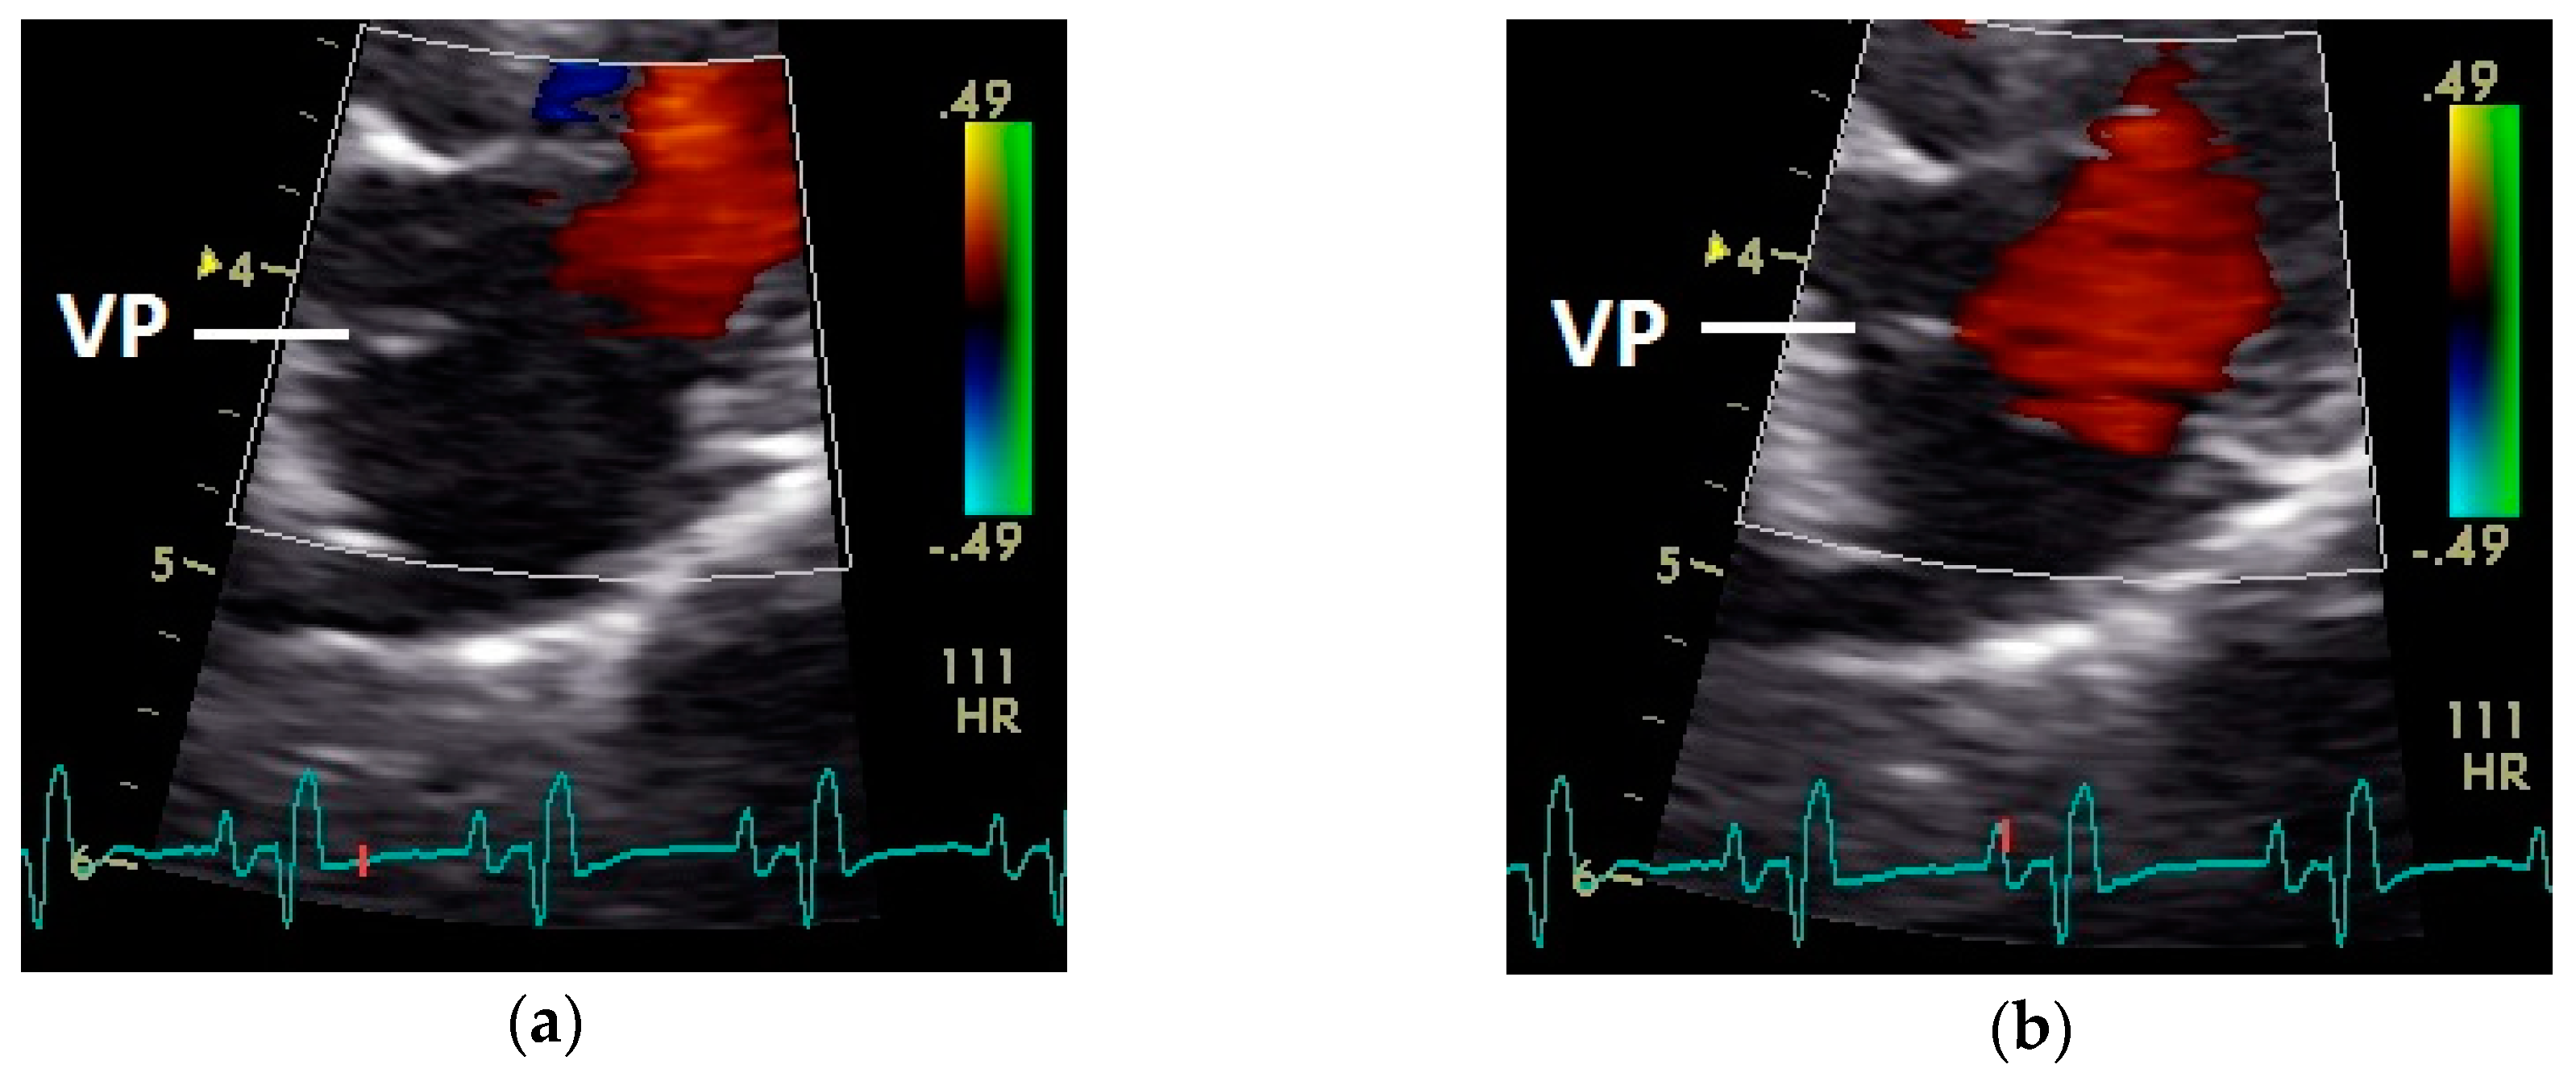

After the P wave of the ECG in the phase of the relaxation of myocardium of the left atrium, a little blue filling signal over the AV valve was seen in the some pigeons (n = 27; 62.8%) with the used settings (Figure 5). In all pigeons a later and faster blue inflow signal in the atrium in the time of the descending part of the T wave was recorded over the AV valve to the left part of the atrium (significant difference Chi-squared test p ≤ 0.001). At the same time a red signal was seen right and left from the valva pulmonis in some pigeons (25 out of 43 birds; 58.1%; Figure 6). The position of the valva pulmonis was almost constant in diastole (Figure 7) and systole (Figure 5 and Figure 6).

Figure 7.

Position of the valva pulmonis (VP) in the diastole: (a) passive and (b) active ventricular filling (red signal); HR: heart rate; color scale of the color Doppler image is calibrated in m s−1.

Constant simultaneous occurrences of red and blue color in the Doppler images of ventricles and atria show the presence of typical constant blood flow vortex formations in the avian heart, comparable to the mammalian heart [32]. Vortices in the cardiovascular system are supposed to play fundamental roles in normal physiology and provide a proper balance between blood motion and the stresses on the surrounding tissues [32]. In the color Doppler examinations of the pigeon heart in the “four-chamber view”, a vortex clockwise in the left atrium and counter-clockwise in the right atrium were observed. In this context the valva pulmonis of the left atrium is discussed as an important anatomical structure for sealing the atrial cavum [1]. However, the color Doppler images in our investigation show that in diastole (atrial contraction) and systole (atrial filling) the position of the valva pulmonis is very constant. There is no evidence for a motion of this valve which could contribute to the closure of the left atrium (see Figure 5, Figure 6 and Figure 7). The main function of this anatomical structure seems to be to direct blood flow towards the left ventricle (see Figure 6). The passive filling of the atria was visible after the P wave of the ECG as a cause of the relaxation of the myocardium and in the time of the end of the T wave of the ECG as a cause of the ventricular pump mechanism by the myocardial contraction in the systole. The findings in the color Doppler sonographic examination of the ventricles allow the conclusion of the presence of an asymmetric vortex ring in the left ventricle in the passive and active ventricular filling with a stronger vortex behind the longer septal part of the left AV valve (see Figure 1, Figure 2 and Figure 3). It is possible that an asymmetric valve shape allows a typical vortex formation (larger vortex in the direction of the outflow tract) that enables a faster blood flow and emptying of the ventricle [33]. Similar vortex formations in the left ventricle are described in the mammalian heart [32,33]. In the right ventricle the active ventricular filling leads to a great counter-clockwise blood vortex in this ventricle. The blood flow behind the right AV valve in the active ventricular filling as well as the active movement of this muscular valve during the closure seem to be important for the development of this blood flow vortex (see Figure 8). In connection with the asymmetrical shape of the right ventricle and oblique arrangement of the right AV valve [1], the shape of the blood vortex simplifies the outflow of blood through the pulmonary artery.